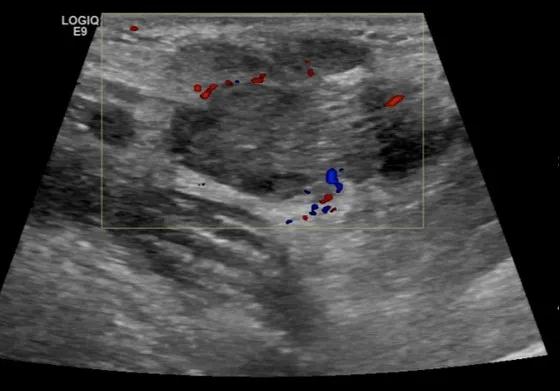

第四例是胸腺癌化妆包,术后、化疗之后淋巴结转移,肿块范围巨大,99mm*61mm,边界不清,呈浸润状,肿块包绕颈动脉,颈内静脉压闭,症状明显。由于患者放化疗也不敏感、血供非常丰富,于是采取多点姑息性消融。姑息性消融后未实现完全消融,病灶大片坏死,肿胀疼痛得到明显的缓解,后续患者未再来复查。

(病例4图例)